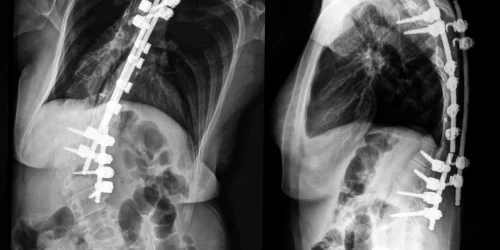

A Medtronic spinal cord stimulator is a small, battery-operated device that is implanted under the skin in the lower back. The device sends electrical impulses to the spinal cord to block pain signals from reaching the brain.

A Medtronic spinal cord stimulator is implanted under the skin in the lower back. The implantation procedure is done in a hospital setting and typically takes less than an hour. You’re given general anesthesia so you don’t feel any pain during the surgery.

Can I have CT scans and X-rays?

Yes, you can have CT scans and X-rays with a spinal cord stimulator. However, you will need to notify your doctor ahead of time so that they can take special precautions.